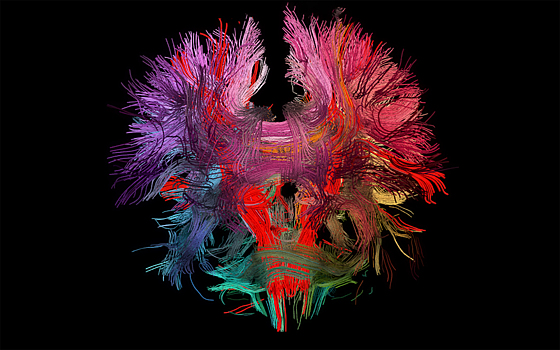

Исследователи нашли механизм, благодаря которому мозг определяет, какие соединения между нейронами нужно надолго сохранить и укрепить. Статья об этом принята к публикации в журнале Cell Reports. Синапсы — важнейший компонент структуры мозга, место соединения нейронов и передачи электрического импульса от клетки к клетке. Но не все синапсы сохраняются надолго. Главный критерий отбора синапсов основан на том, насколько хорошо они отвечают на обусловленную опытом нейронную активность, но как такой отбор реализуется на молекулярном уровне, было неясно. В новом исследовании нейробиологи Массачусетского технологического института выявили ген и белок CPG15, который отвечает за сохранение образовавшегося синапса. В своей работе ученые использовали метод двухфотонной микроскопии выского разрешения для анализа структуры мозга мышей. Сравнивая наблюдения, сделанные у нормальных мышей и тех, которые были созданы без белка CPG15, исследователи смогли показать, что белок необходим для того, чтобы «укрепить» новые синапсы. Команда отслеживала специально помеченные нейроны в зрительной коре мышей после нормального зрительного опыта и после двух недель в темноте. К своему удивлению, они увидели, что синапсы обычно возникают, а затем исчезают с одной и той же скоростью, независимо от того, были ли мыши на свету или в темноте. Тщательное исследование подтвердило, что опыт не имеет значения для формирования дендритных шипиков — структур, которые позволяют образовывать синаптическое соединение. Это опровергает распространенное предположение, согласно которому опыт был необходим даже для появления дендритных шипиков. Затем ученые проверили, как влияет на образование новых синаптические соединений белок CPG15. Оказалось, что эта молекула вызывает выработку другого белка — PSD95, который отвечает за сохранение синапса. Позже ученые попробовали другой эксперимент, проверяя, может ли повысить низкую выработку PSD95, которая наблюдается, когда нормальные мыши находятся в темноте. Действительно, при введении белка CPG15 уровень PSD95 поднялся, как будто животные были подвержены визуальному опыту. Это показало, что CPG15 не только несет сообщение опыта на свету, он может фактически заменить его в темноте, «обманывая» PSD95. Понравился материал? Добавьте Indicator.Ru в «Мои источники» Яндекс.Новостей и читайте нас чаще.